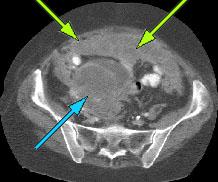

HELICAL CT FINDINGS: The CT was performed on AIC’s multi-slice helical CT (MSCT) scanner. Images with 5 mm collimation were obtained before, immediately following and 5-10 minutes after power injection of IV contrast. Fig. 1 demonstrates large bilateral pleural effusions (red arrows) with secondary compressive atelectasis of the lower lobes (yellow arrow). Fig. 2 shows large amount of ascites (arrows). Fig. 3 shows a large heterogeneous complex pelvic mass (blue arrow) and a large amount of peritoneal masses consistent with omental metastasis known as “omental caking” (green arrows).

DIAGNOSIS: The CT images are suggestive of ovarian carcinoma and metastatic peritoneal implants.

DISCUSSION:Omental cake” is a description given to thickening of the greater omentum secondary to omental peritoneal metastasis. Other forms of peritoneal metastasis include mesenteric increased density and networking, lobulated mass in the pouch of Douglas, adnexal mass of cystic or soft tissue density (“Krukenberg tumor”), lobulated fluid collection in peritoneal cavity, massive ascites. Krukenberg tumor is a metastatic tumor to the ovaries from GI tract cancer (stomach, colon, pancreas, and biliary tract). It can antedate the discovery of the primary lesion in up to 20%.